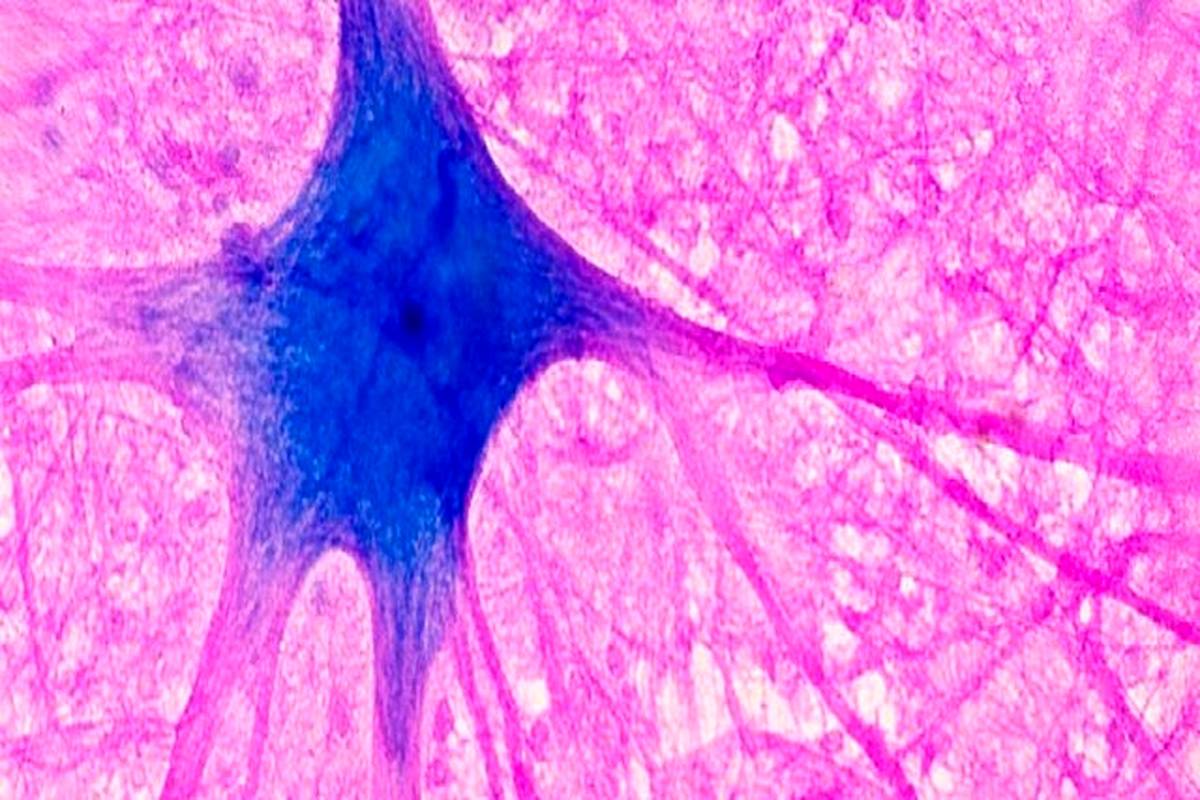

«متیلن بلو» میتواند از مانع حفاظتی اطراف مغز(سد خونی مغز) عبور کند و وارد آن شود. دانشمندان همچنین دریافتهاند که این ماده میتواند از «میتوکندریها»(mitochondria) که بهعنوان موتورهای سلولی توصیف میشوند، محافظت و پشتیبانی کند. این ماده ممکن است به «میتوکندریها» کمک کند تا انرژی را برای استفاده سلولها تولید کنند. به همین دلایل، دانشمندان در حال مطالعه تأثیر «متیلن بلو» بر مغز هستند.